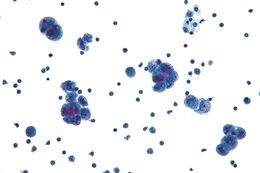

显微镜下的浆液性癌,是一类病发于输卵管的癌症 |

最常见的癌症类型是恶性腺瘤,在一项科学显示中,3051名患者中有88%的属于这种类型[2]。在这类人群中,一半以上的都是未分化的、89%是单侧肿瘤;其中原发性、区域性和转移性各占三分之一。极少的输卵管瘤中包含平滑肌肉瘤和移行细胞癌。